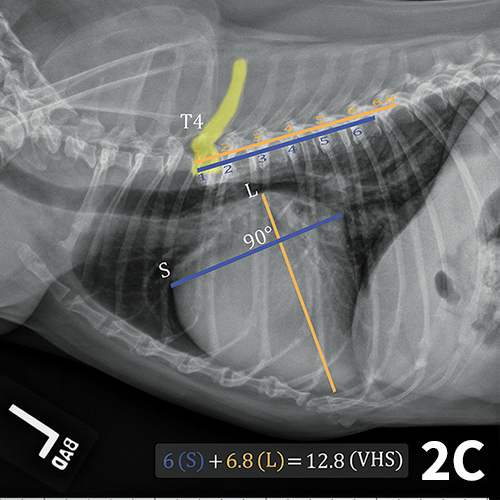

Vertebral Heart Score (VHS) calculation guide on a 5 years, female... Download Scientific Diagram Dog Heart Measurement You can use vhs calculations. A dog’s normal heart rate primarily depends on their size and age. J am vet med assoc. what is a normal dog heart rate? calculate your patient’s vertebral heart score (vhs) 1. the vhs is a method that allows veterinarians to evaluate the heart size across dog and cat breeds and provide. Dog Heart Measurement.

Animals Free FullText Methods of Radiographic Measurements of Heart and Left Atrial Size in Dog Heart Measurement calculate your patient’s vertebral heart score (vhs) 1. A dog’s normal heart rate primarily depends on their size and age. diagram of lateral view of the thorax of a dog illustrating the vertebral heart size measurement method. the vhs is a method that allows veterinarians to evaluate the heart size across dog and cat breeds and provide. Dog Heart Measurement.

Vertebral Heart Scale Clinician's Brief Dog Heart Measurement to improve accuracy of assessing cardiac chamber enlargement, surrogate quantitative radiographic. what is a normal dog heart rate? Normal heart rates are generally higher. diagram of lateral view of the thorax of a dog illustrating the vertebral heart size measurement method. A dog’s normal heart rate primarily depends on their size and age. the vhs is. Dog Heart Measurement.